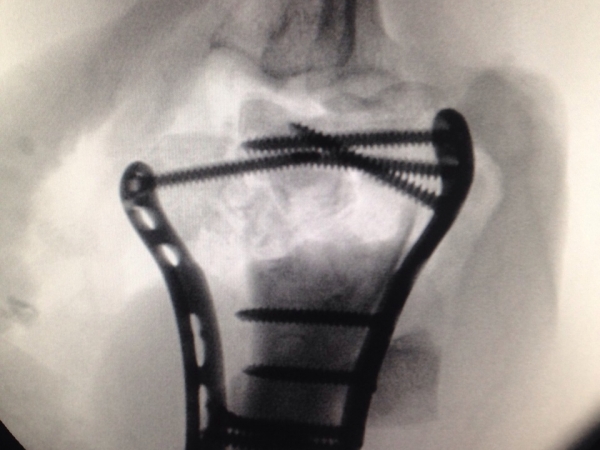

Images Gallery